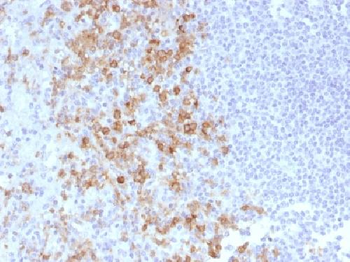

Formalin-fixed, paraffin-embedded human Spleen stained withCD162 Monoclonal Antibody (PSGL1/1601).